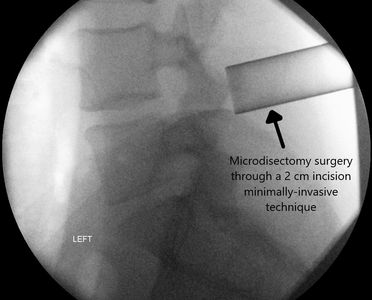

Minimally-Invasive Lumbar Decompression and Microdiscectomy

We provide videoconferencing consultations using telehealth and will show you your actual CT or MRI images and explain the findings in relation to your back pain and sciatica symptoms.